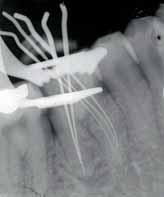

posteriorly on the left palate till the posterior vibrating line. There was no pointing of the lesion. IOPA and occlussal radiographs were taken (Fig1a & b). The IOPA revealed a huge radiolucent lesion with diffuse margins in relation to the periapical region of the upper left lateral which had a root canal filling and a separate smaller radioluscent periapically to the adjacent central incisor also. The occlussal radiograph showeda large radiolucent lesion on the palatal aspect in relation to the upper left lateral. It was decided to retreat the case and the patient was advised of the poor prognosis of the tooth.

Fig 1a: First visit (IOPA) Fig 1b: first visit (occlussal) Fig 2a: Pre obturation 14 months (IOPA) Fig 2b: Pre obturation 14 months (occlussal)

hypochlorite and hydrogen peroxide and then washed with saline. A closed dressing with calcium hydroxide was given and patient recalled after one month. Thereafter, periodic monthly appointments were given where the canal was irrigatedand closed irrigation with calcium hydroxide was given. After around 14 months after the first visit the swelling was completely absent and patient reported no pain. The periapical radioluscency was still present though localized to the periapical and reduced to around 5mm in diameter (Fig2a & b). This time the canals were obturated using lateral condensation technique (Fig 3). And the patient recalled after six months for a review. Six months after obturation it was seen that the periapical radioluscencywas almost absent with a mild crescent shaped radioluscent around the apex (Fig 4a & b). The patient had no symptoms to report. During the intervening six months the patient had crowns made to correct the discoloration. The patient was recalled after a period of six months to further review the healing.

One year after obturation the patient had absolutely no signs and no symptoms. The occlussal radiograph and periapical radiograph showed a very thin crescent shaped radioluscency at the apex (Fig 5).